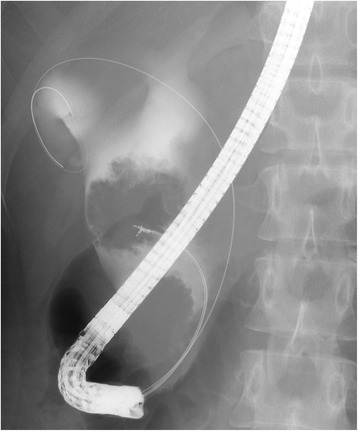

Abdominal ultrasonography revealed a cystic dilatation of the extrahepatic bile duct and two protruding tumors in the lumen of the dilated common bile duct (Fig. 1). Doppler ultrasound detected a blood flow signal within the tumor. Abdominal computed tomography (Fig. 2) demonstrated a cyst within the common bile duct measuring 7 cm in diameter and two enhanced tumors measuring 4 cm in diameter located in the inferior bile duct and middle bile duct. Magnetic resonance cholangiopancreatography (Fig. 3) clearly demonstrated a cystic dilatation of the extrahepatic bile duct (Todani’s CBD classification: type 4-A) [ref. 1]. Endoscopic retrograde cholangiopancreatography (Fig. 4) also demonstrated a cystic dilatation of the bile duct as well as the presence of two tumors. Biopsy of one of the tumors confirmed the presence of adenocarcinoma. Amylase, CA19-9, and carcinoembryonic antigen levels in the choledochal cyst were 54,722 IU/l, 230,853 U/ml, and 3.051 ng/ml, respectively.